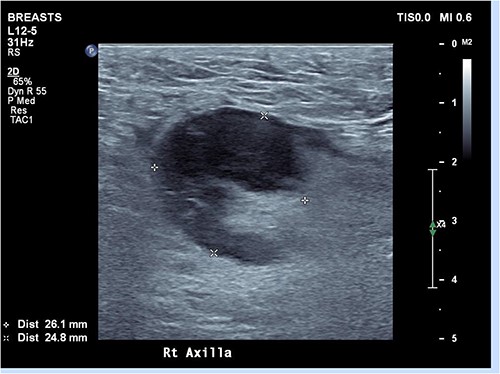

Ultrasound of the right axillary mass indicated a single enlarged lymph node measuring 26 × 25 × 40 mm (Fig. 1). Following discussion with haematology and infectious disease specialists, a nodal core biopsy was performed. This identified an atypical lymphoid infiltrate primarily characterized by CD138+/IRF4+ plasma cell clusters, interspersed by CD3+/CD5+ T cells and scattered necrotic foci (Fig. 2). As this was a core biopsy, nodal architecture was not appreciable. There was mild positivity for plasma cells on EBV-encoded small RNA in situ hybridization (EBER-ISH), consistent with the patient’s positive EBV PCR status. Bacterial and fungal specimen culture was negative, including for Mycobacterium tuberculosis, and flow cytometry did not detect any monotypic B cells or aberrant T cells.

Ultrasound of right axilla showing an enlarged right axillary lymph node. This node retained its fatty hilum but had thickened cortex, measuring up to 13 mm in short axis.